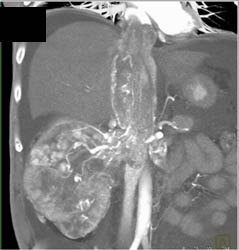

Coronary Artery Anatomy for LAD in Various Renderings